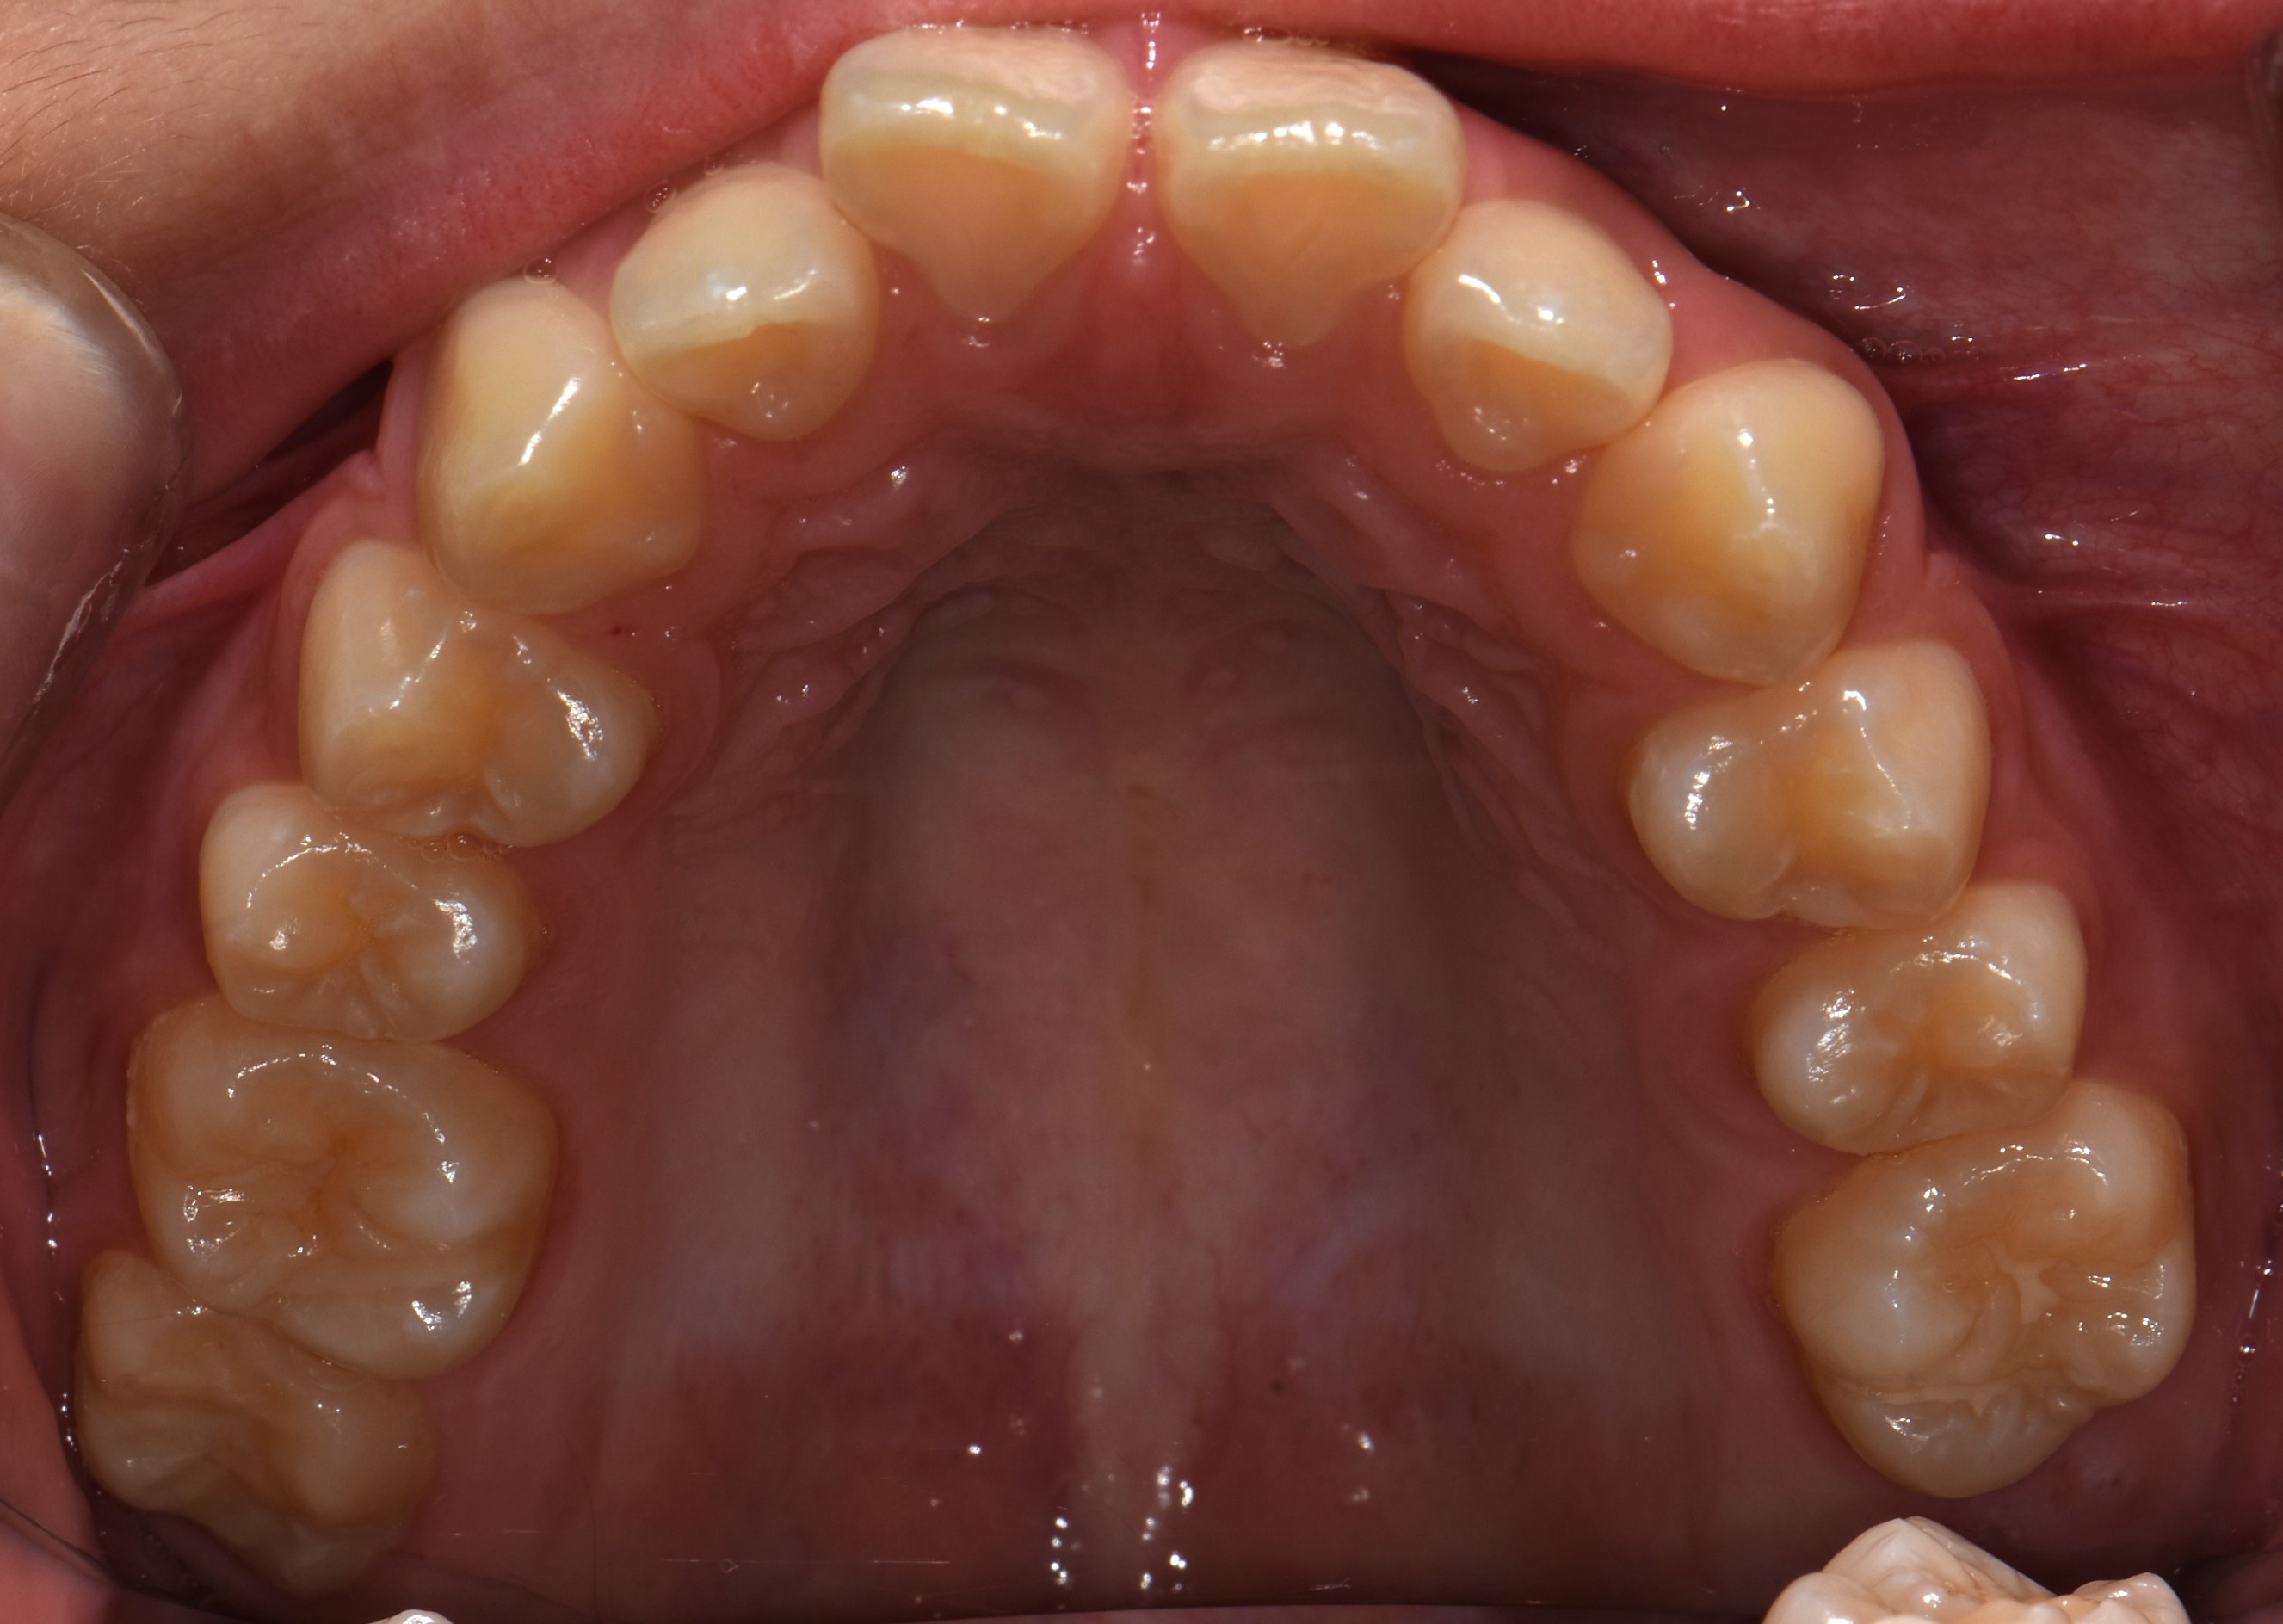

치료 전 사진입니다.